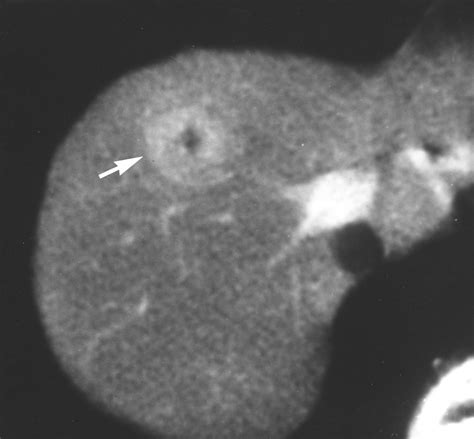

The hallmark of Focal Nodular Hyperplasia is the presence of a central fibrous scar. When radiologists view this mass through imaging technology, this central scar is a key diagnostic feature that helps distinguish it from other types of liver growths, such as hepatocellular adenomas or malignant carcinomas.

• MRI (Magnetic Resonance Imaging): This is the gold standard for diagnosing Focal Nodular Hyperplasia. Using specific contrast agents (like gadoxetate disodium), doctors can observe the unique way the mass absorbs and excretes the contrast, which is highly characteristic of FNH.

• CT Scan: Often shows a typical arterial enhancement pattern.